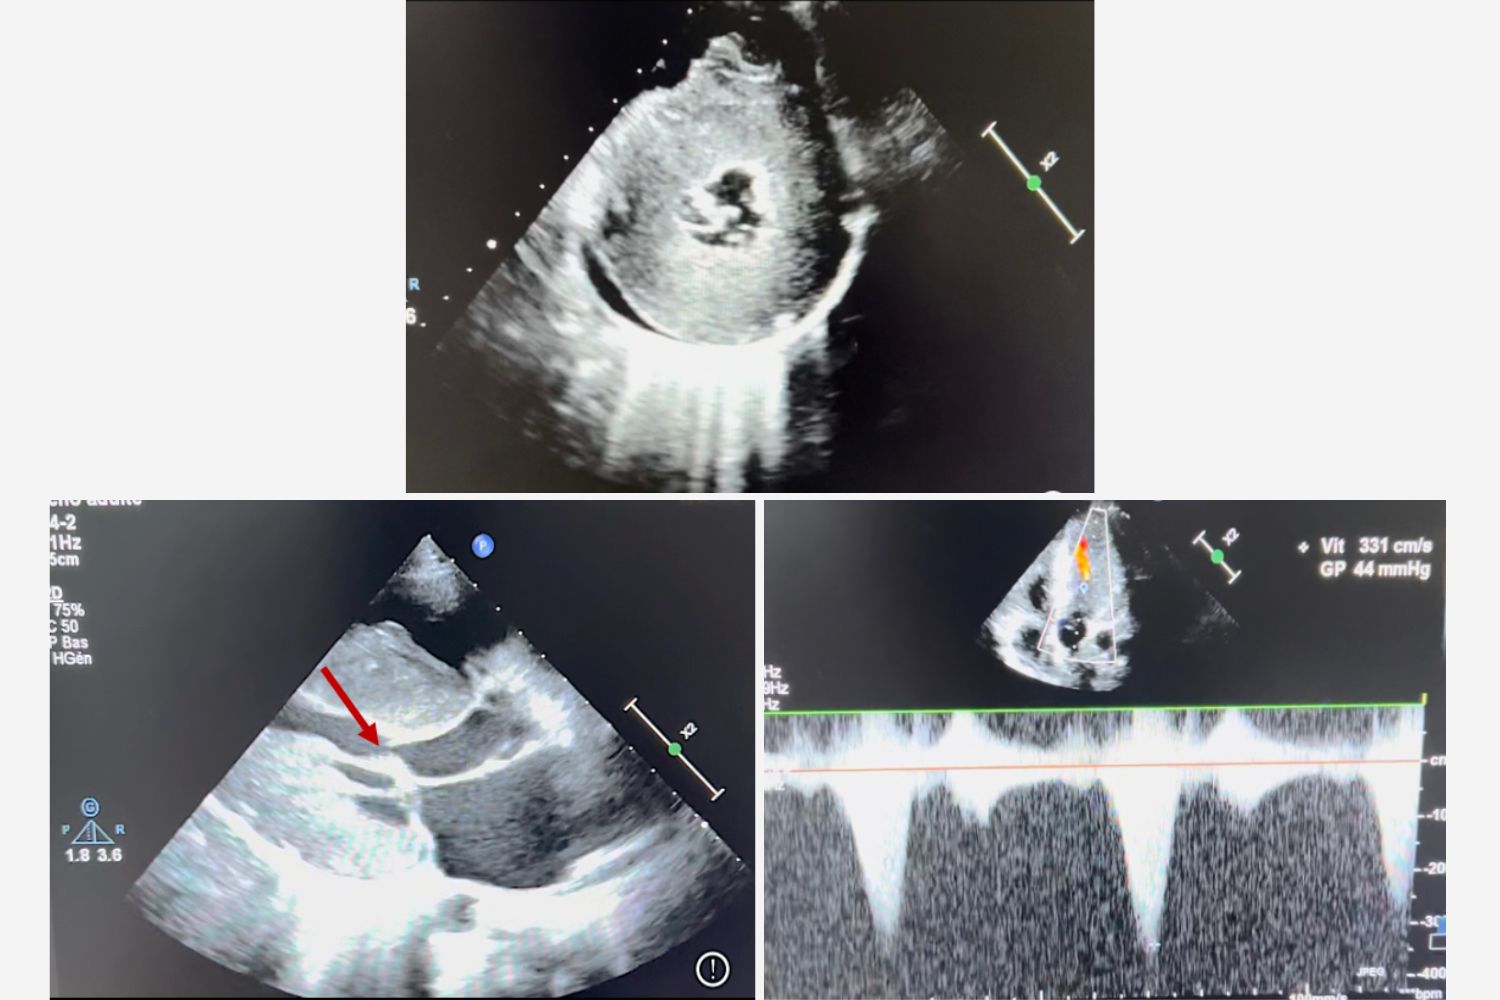

Image of the Week - 17 December 2025

Image of the week